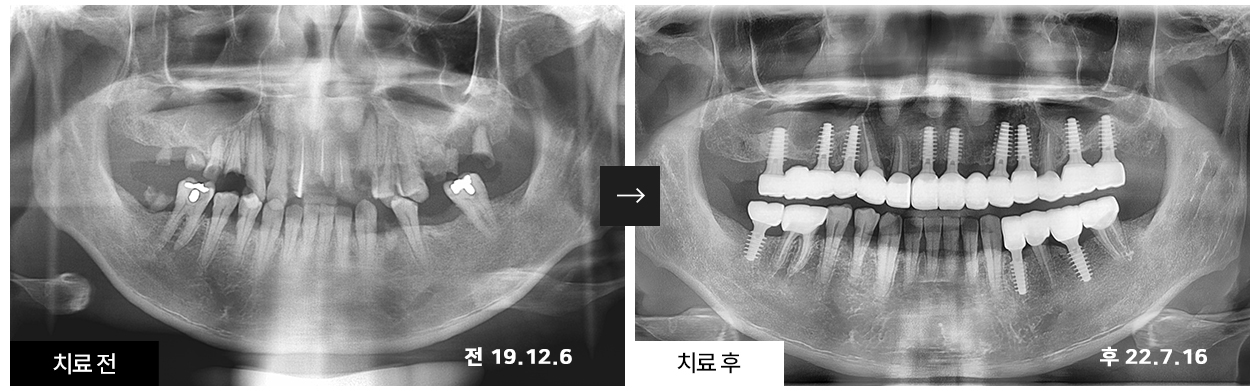

서울 0.1치과에서 치료받으신 환자분들의 치료 전/후 비교사진입니다.

본 이미지는 환자의 동의를 얻어, 동일 환경에서 촬영하였습니다.

시술, 수술 후에는 개인에 따라 출혈, 염증, 감염 등 부작용이 발생할 가능성이 있으므로 세심한 주의가 필요합니다.

의료진과 상담 후 결정하시기 바랍니다.